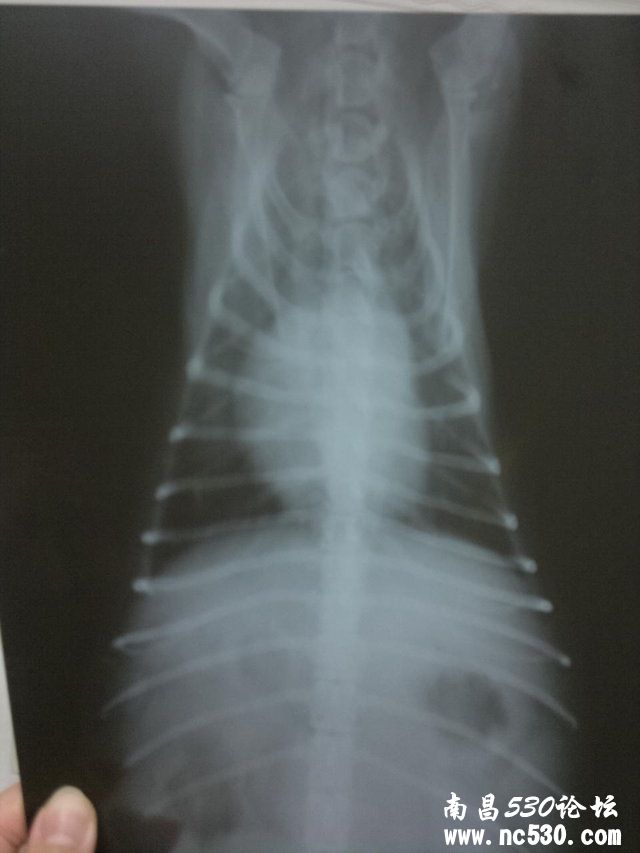

2011-12-24 01:18    动物种类:狗 动物品种:京巴串

动物年龄:11

性别:母

免疫情况:二个月时打过五联疫苗以后没有再打过

是否绝育或去势:否,下过六窝仔,七岁以后就没再让下过.

精神状态:不如以前精神

食欲如何:不想吃饭

排便如何:正常,一天最少二回,形状颜色都很好 症状:大概有一个月了,没精神总爱趴着,有时呼吸间身体有轻微拌动,睡觉有时会喘几下,溜弯时不爱走近几天不爱吃饭. 12月18日在家附近的宠物诊所诊断说心肌肥大,第二天发现外阴流脓水诊断子宫蓄脓,后有医生说开放型的叫子宫内膜炎,现在打消炎针.

麻烦张医院给看看下边的片子12月18日拍的,因为我们这边没有正规的宠物医院还劳烦张医生给确诊下

这个是心脏病吗是哪种呢需要怎样治疗,可以吃药吗,吃哪种药比较好.还有心脏病的话可以输液吗?